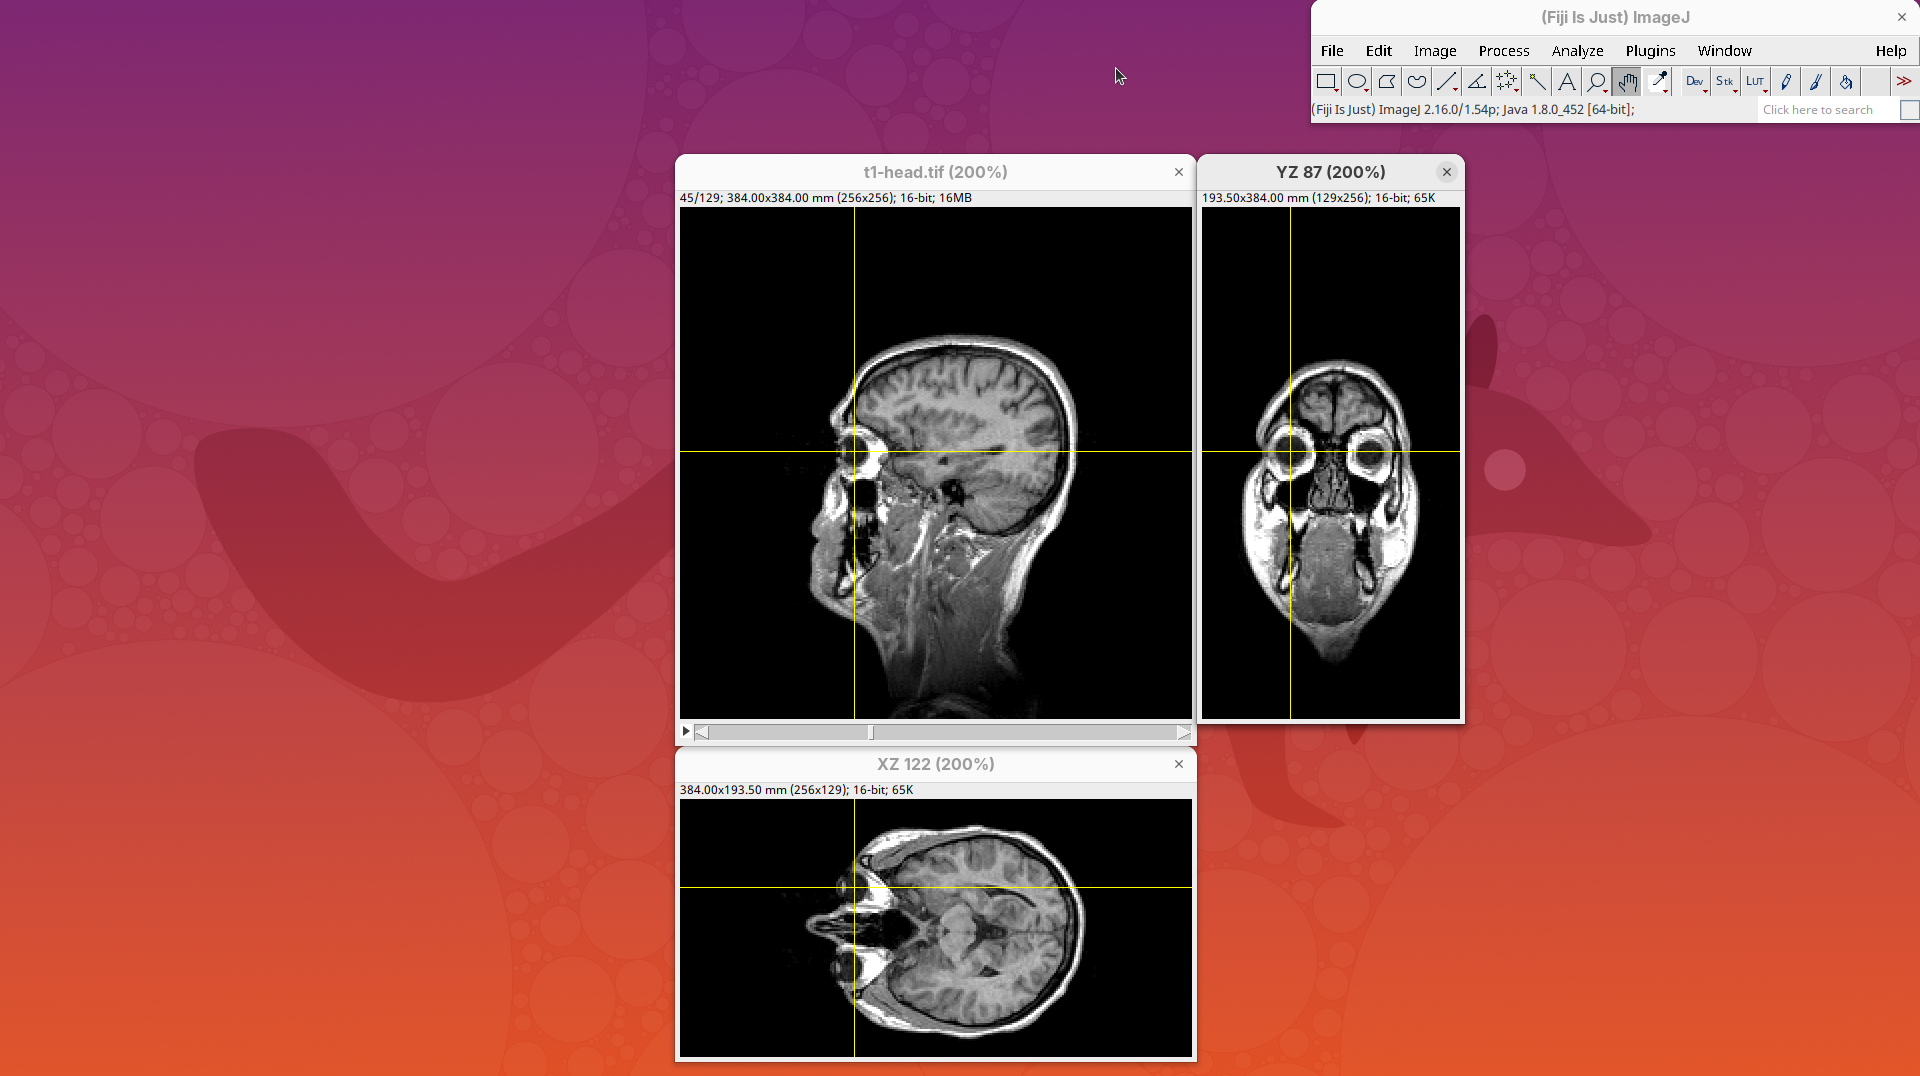

Orthogonal Views

Orthogonal Views is a tool that shows the optical sections through the orthogonal planes of XY: XZ and YZ. It is an easy and quick way to get a sense of the tridimensionality of your dataset. Whenever I’m opening a dataset for the first time I use Orthogonal Views. To activate it:

- Click on

Image>Stacks>Orthogonal Views(or pressCtrl+Shift+H). - The XZ and YZ panels will open next to your XY stack.

- The yellow lines are synchronized between the panels.

- Click around the different parts of the head to inspect the same position under different angles.

Orthogonal Views is a great way to start understanding your 3D data.